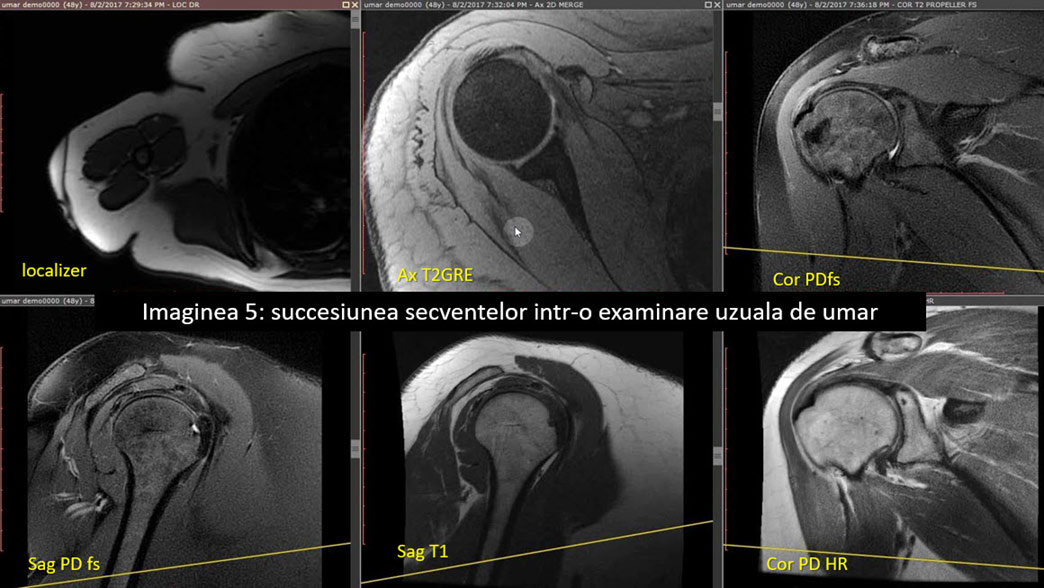

Secvențele IRM umăr uzual